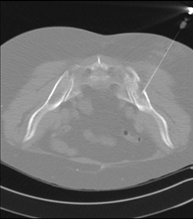

Prova que consisteix en obtenir una mostra de teixit de lesions toràciques, com per exemple masses pulmonars, mediastíniques, lesions òssies, etc. Per això s'administra anestèsia local sobre la zona de punció, que es realitza amb agulles de calibre fi. Tot el procediment es realitza controlat amb imatges obtingudes per tomografia computaritzada (TC) en diversos moments de la punció, mitjançant un equip de Fluoroscòpia-TC. Després de la prova, el pacient resta unes hores hospitalitzat. És necessari portar proves de coagulació abans de la punció. - Biòpsia tòrax guiada per TC

Consisteix en obtenir una mostra de teixit d'una determinada lesió toràcica, com per exemple del pulmó, del mediastí, de l'estern, etc. A vegades es realitza sota sedació, amb l'ajuda de l'equip d'anestèsia. S'utilitzen agulles que permeten l'obtenció d'un cilindre de la lesió a estudiar que s'enviarà a Anatomia Patològica per a la seva anàlisi histològica. Tot el procediment es realitza controlat amb imatges obtingudes per tomografia computaritzada (TC) en diversos moments de la biòpsia, mitjançant un equip de Fluoroscòpia-TC. Després de la prova, el pacient resta hospitalitzat per controlar la seva evolució. És necessari portar proves de coagulació abans de la punció. - TC Columna Dorsal

Prova que consisteix en obtenir una mostra de teixit de lesions toràciques, com per exemple masses pulmonars, mediastíniques, lesions òssies, etc. Per a tal s'administra anestèsia local sobre la zona de punció, que es realitza amb agulles de calibre fi. Tot el procediment es realitza controlat per imatges obtingudes per Tomografia Computaritzada (TC) en diversos moments de la punció mitjançant l'ús de Fluoroscòpia- TC. Després de la prova, el pacient resta unes hores hospitalitzat. És necessari que porti les proves de coagulació abans de la punció. - Biòpsia de tòrax guiada per TC

Consisteix en obtenir una mostra de teixit d'una determinada lesió toràcica, com per exemple del pulmó, del mediastí, de l'estern, etc. A vegades es realitza sota sedació, amb l'ajuda de l'equip d'anestèsia. S'utilitzen agulles que permeten l'obtenció d'un cilindre de la lesió que s'ha d'estudiar, que s'enviarà a Anatomia Patològica per a la seva anàlisi histològica. Tot el procediment es realitza controlat per imatges obtingudes per Tomografia Computaritzada (TC) en diversos moments de la biòpsia mitjançant l'ús de Fluoroscòpia-TC. Després de la prova, el pacient resta hospitalitzat per controlar la seva evolució. És necessari que porti proves de coagulació abans de la punció. - PAAF (Punció) abdominal guiada per TC